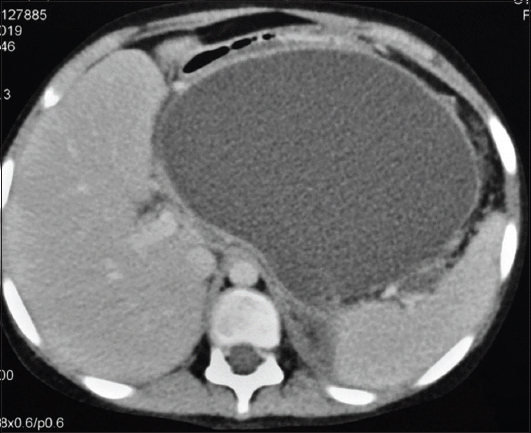

A 12-year-old child, a known case of idiopathic acute necrotizing pancreatitis, presented with upper abdominal pain and fever. Ultrasound and computed tomography of the abdomen revealed a large walled-off pancreatic necrosis (WON) in the lesser sac (Fig. 1). Endoscopic ultrasound (EUS)-guided transmural drainage of the WON was attempted using a conventional curved linear array echoendoscope (GF-UCT 180; Olympus Medical Co. Ltd.). However, the echoendoscope could not be negotiated across the gastroesophageal junction (GEJ) because of extrinsic compression by the WON resulting in acute angulation. Repeated attempts, including an attempt to pass the scope over a guidewire coiled in the stomach, were unsuccessful. Therefore, we decided to use the forward-viewing linear echoendoscope (TGF-UC 180J; Olympus Medical Co. Ltd.). This scope was able to safely traverse the GEJ under direct endoscopic vision while still experiencing significant resistance. Under EUS guidance, the WON was punctured with a 19-G needle. A guidewire was then coiled inside the WON and the access site was dilated using 4-mm biliary balloon dilator (Fig. 2A). Subsequently, a 14 mm wide fully covered bi-flanged self-expanding metallic stent (SEMS) was deployed under EUS (Fig. 2B) and fluoroscopic guidance (Fig. 2C). Following drainage, the child showed a marked improvement in symptoms. The SEMS was removed 3 weeks later following complete resolution of the WON.

Figure 1 Computed tomography of the abdomen, showing a large walled-off necrosis